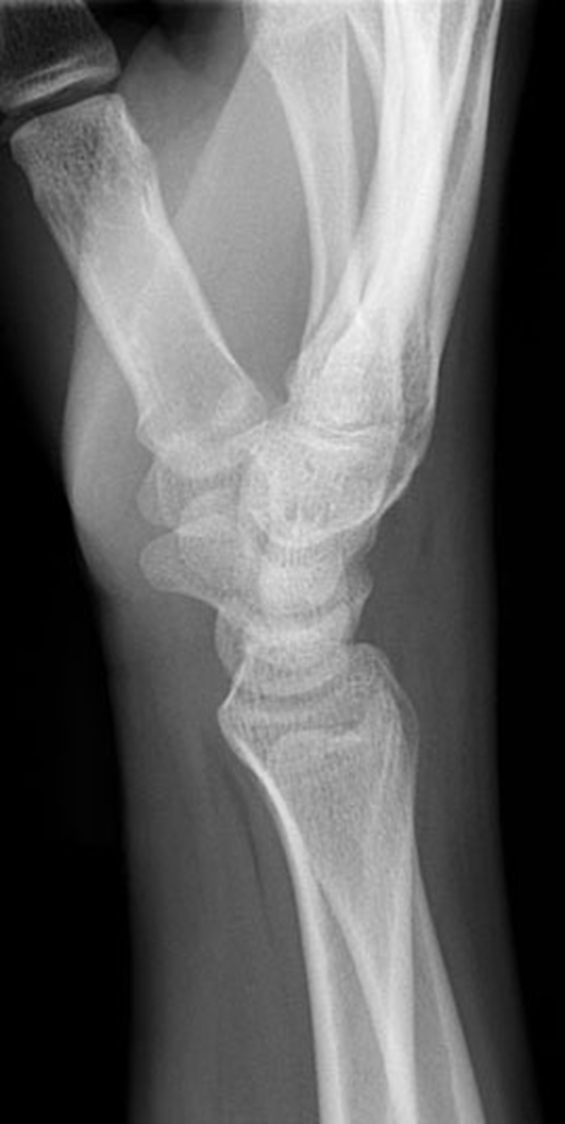

what view is this?

lateral wrist